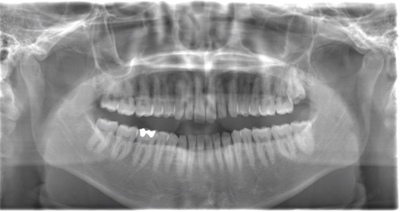

CASE 1

| 年齢・性別 | 30代・女性 |

| 主訴 | 左右に分けて親知らずを抜きたい、できれば痛くなく抜きたい |

| 親知らずのはえ方 | 完全に出ていてまっすぐはえている |

| 抜歯期間 | 15分 |

| 抜歯費用 | 約2,000円(保険内) |

| 抜歯内容 |

何度か虫歯になり痛みはないが早めに抜きたい。 完全に頭が出ているため歯ぐきを切ったり骨を削らずに抜歯しました。 根の形も単純なため抜歯自体は5分もかからず上下ともに終わりました。 術後痛みや腫れも出ていません。 抜歯後は感染をしやすいため必ず抗生物質を飲み切ってください。 |